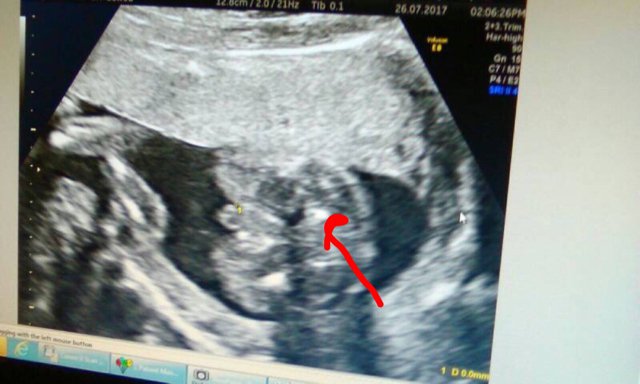

Sorry I can't seem to like with my previous thread. Pls look at this and tell me what u think.techs said boy.ppl r saying girl .

this is whats making me confused ...been told the turtle on top is the boy bit but look at this ..

i would think boy from these pics x

I think boy too